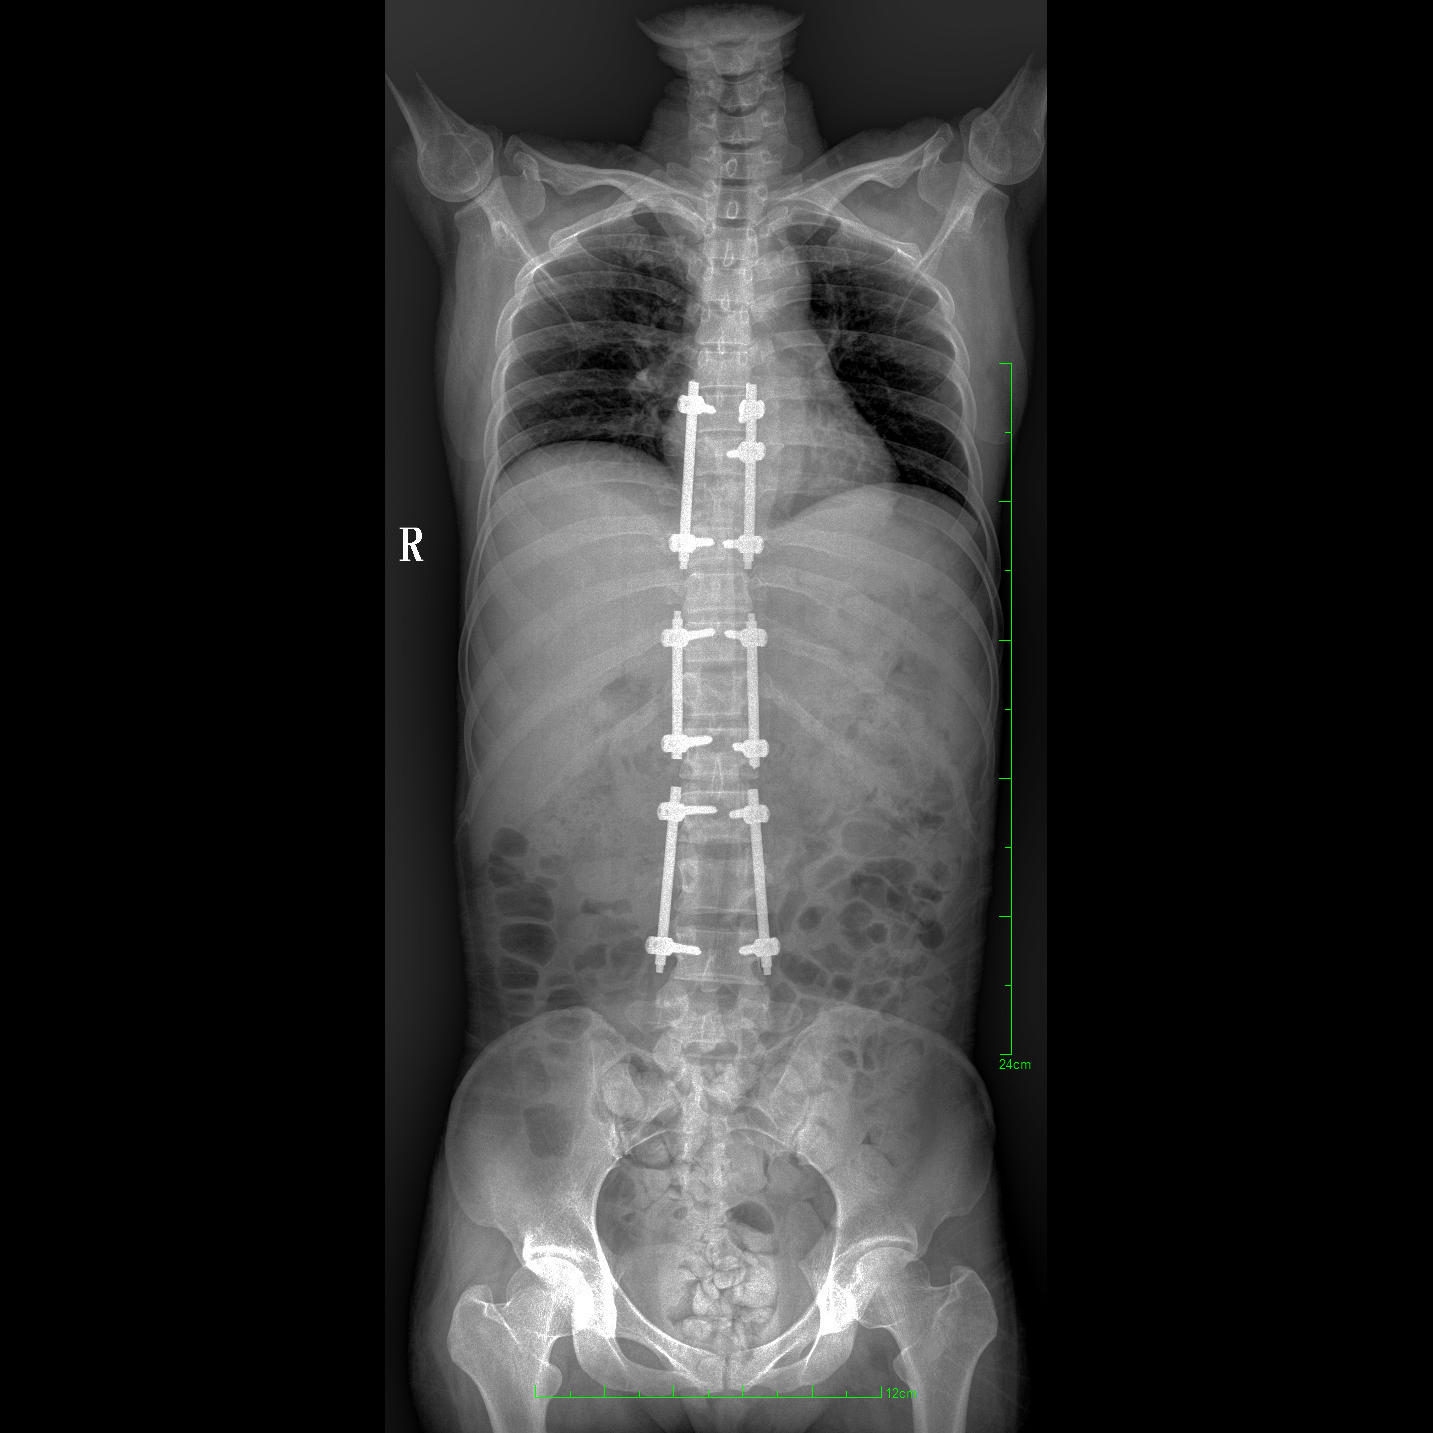

支持全脊柱摄影、双下肢摄影、脊髓造影、复杂创伤、人工关节置换、关节损伤的修复重建等大视野临床应用

全脊柱一次成像 不拼接

17"*34"有效视野,一次成像不拼接。相较于多张摄影再软件拼接的DR设备,PLX8600解决了拼接图像存在密度不均匀,拼接处图像配准和放大效应等问题,给临床带来了大视野影像解决方案,可一次性覆盖全脊柱或双下肢影像。

Clinical picture

临床图片